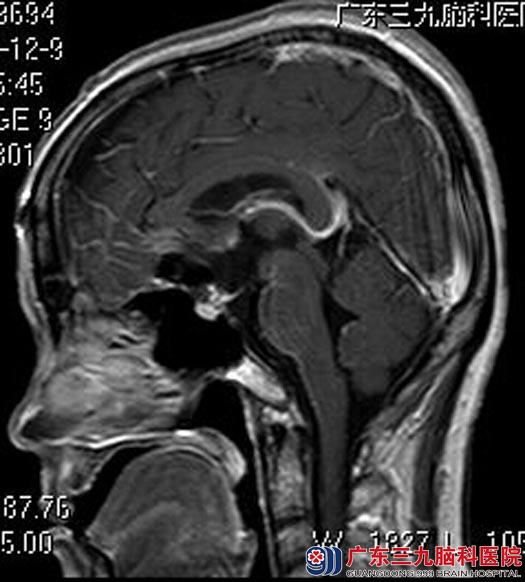

完善相关检查后,由综合神经外科鲁明主任主刀,在全麻下行颅咽管瘤切除术,术中显微镜下见病变呈粉红色部分裸露,有完整包膜,质韧,伴有草黄色囊液,结晶硬块,血供一般,显微镜下切除肿瘤,术中对视交叉和垂体柄均保护完好。术后孙女士未出现尿崩和垂体功能低下等并发症。病理结果提示:颅咽管瘤。

手术后